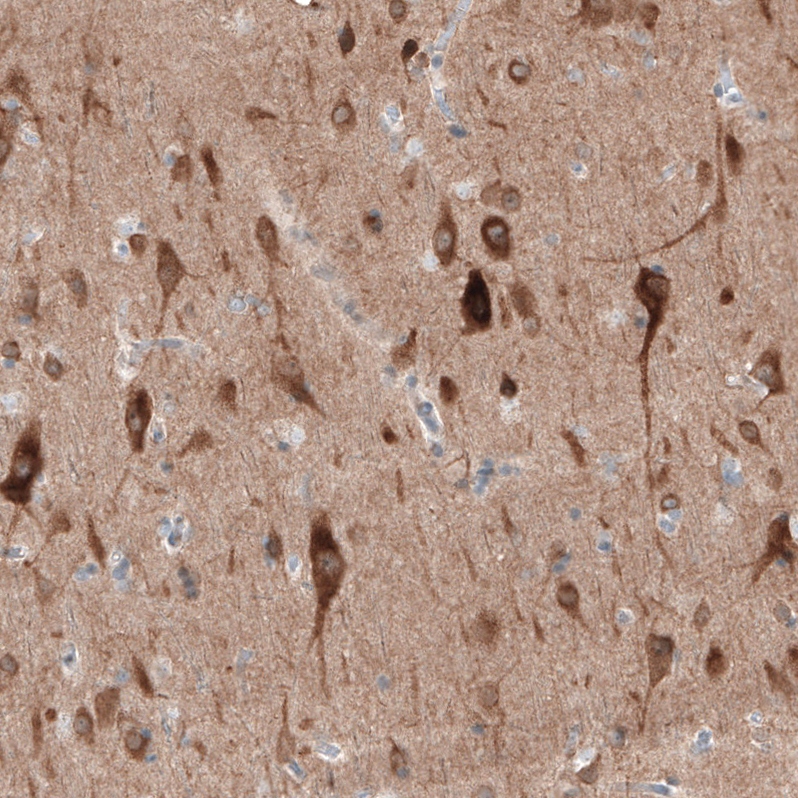

Immunohistochemical staining of human cerebral cortex shows moderate cytoplasmic positivity in neurons.